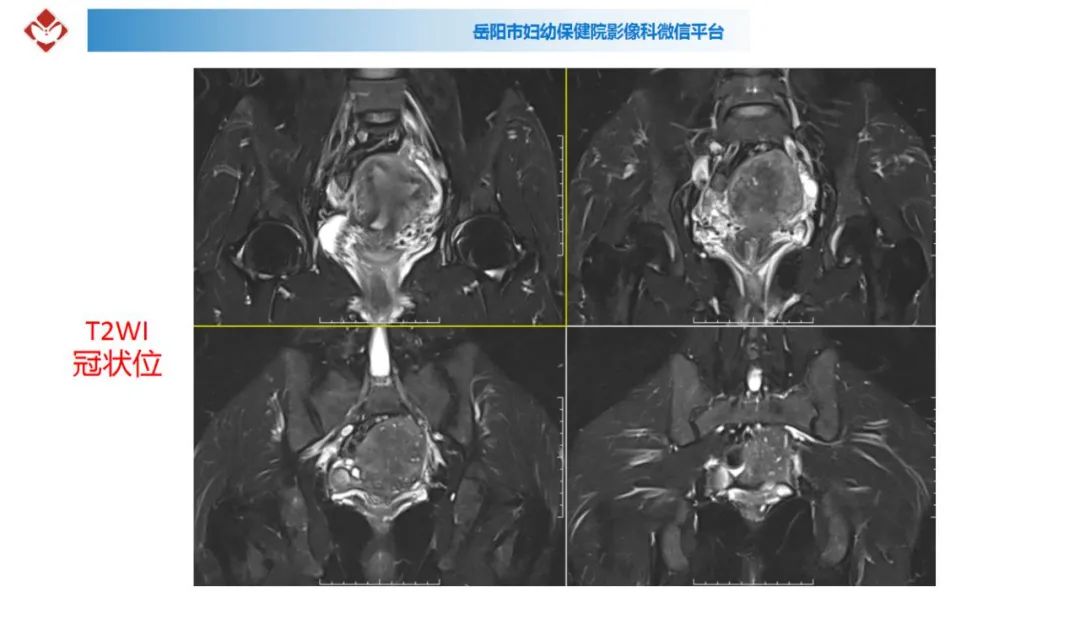

典型疑难病例讨论

来源:岳阳市妇幼保健院影像科